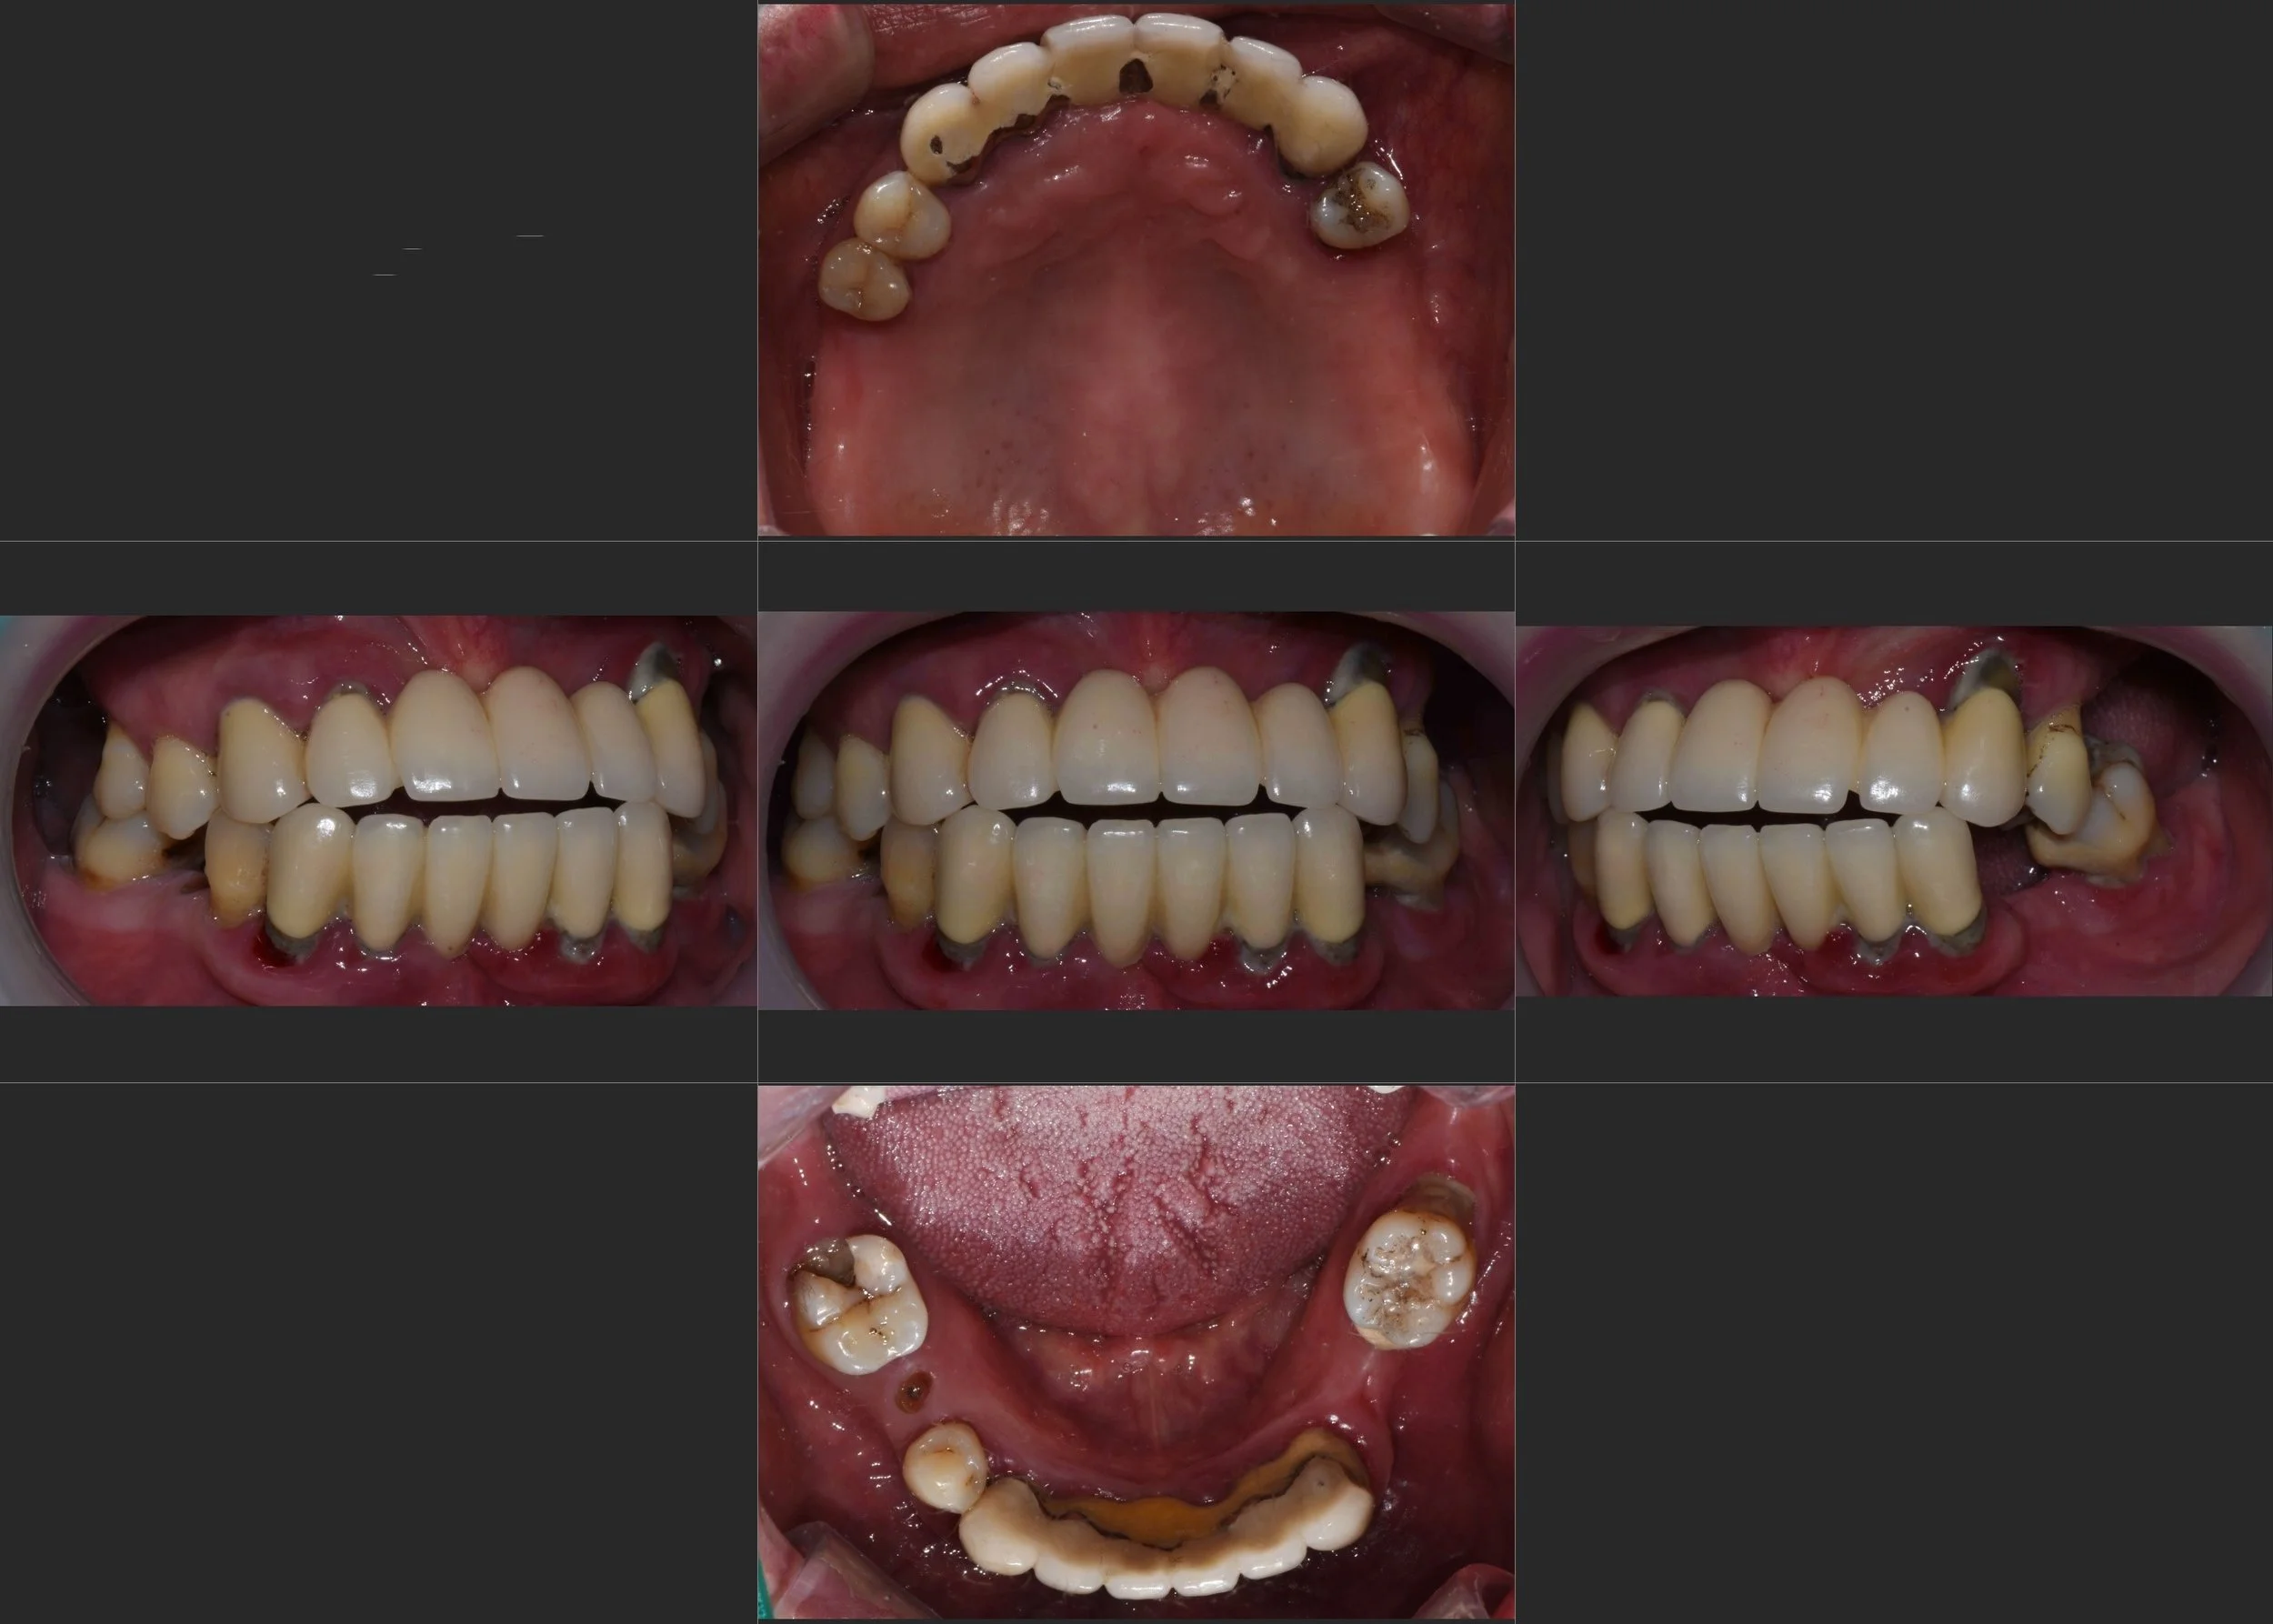

INTRA ORAL - AFTER

4. Final Delivery: High-precision zirconia bridges were delivered in the segmented configuration. The result is a functional, stable, and highly aesthetic outcome that the patient can confidently maintain for years to come.

2. Segmented Prosthetic Philosophy: While a one-piece "Full-Arch" bridge was a viable option, a 3-segment design was intentionally chosen for this case. By dividing the arch into smaller segments, we provided several critical advantages:

• Ease of Maintenance: Better access for interproximal cleaning and hygiene management.

• Mechanical Reliability: Reduced risk of massive failure; if a localized issue occurs, it can be addressed without compromising the entire arch.

• Passive Fit: Improved precision in the prosthetic fit across the resorbed ridges.

3. VDO Stabilization: The patient’s occlusal height was restored, providing necessary support for the facial tissues and restoring masticatory power.